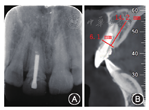

像;B:术前数字化美学分析锥形束CT示11根尖区有圆形低密度影,直径约6 mm,11颊侧骨板完整,厚约1 mm(图2)。

11牙体缺损,慢性根尖周炎。